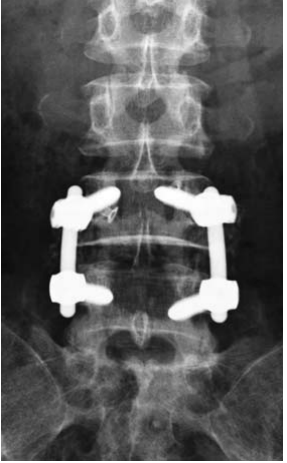

SURGERY

Decompression of L34, L45 and L5S1 were done. L45 through a partial laminectomy of L4 and L34, L5S1 through limited interlaminar approach. L45 was stabilsed with rigid fixation and fusion using pedicle screws, L34 with a dynamic interspinous devices and L5S1 was decompressed only.

This patient illustrates one of many patterns in patients presenting with lumbar spinal canal stenosis and the available options in surgical treatment. Decompression is necessary to relieve nerve compression. Additional procedures often aim to treat back pain or prevent further deterioration and recurrence of symptoms. The commoner options include fusion and soft stabilization. To treat back pain and to prevent deterioration of the spondylolisthesis, L45 fusion was done. At L34, an interspinous device using silicone-based implant allows assisted motion and helps to maintain an open foraminal canal. At L5S1, the small sacral spinous process makes the interspinous device interspinous device ineffective and as fusion was not yet needed, only a decompression was done. DIAM (Medtronics)